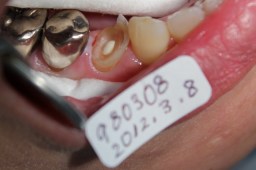

左上のレントゲン写真のイラスト 歯と歯の間の虫歯のため、レントゲンでないと 発見出来ない。 |